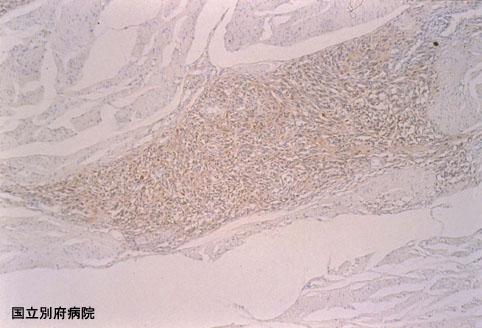

症例提示(所在地,施設名等): 大分県・ 別府医療センター

疾患(病理主体)の分類悪性黒色腫/

部位(臓器別)大腸/直腸

検査方法ミクロ

腫瘍の肉眼分類1型(腫瘤型)/

病変の最大径(ミリ)40以上

腫瘍の深達度ss(a1)